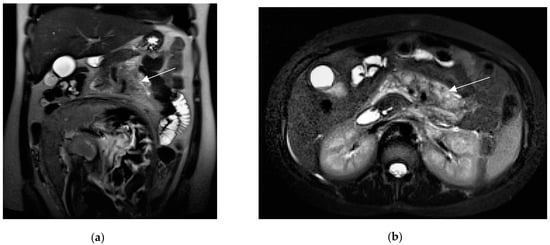

Figure 6.

A 27-year-old pregnant woman with acute abdominal pain and elevated lipase levels (451 UI/mL). Coronal (a) and axial (b) T2-weighted sequences show peripancreatic fat stranding and fluid (arrows), interdigitating through pancreatic parenchyma. These findings are consistent with acute pancreatitis.